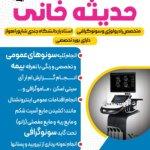

حدیثه خانی

دکتر حدیثه خانی ، متخصص رادیولوژی ، سونوگرافی ،سیتی اسکن و ام ار ای ،دارای بورد تخصصی و استادیار دانشگاه جندی شاپور اهواز.

انجام تمام سونوگرافی های عمومی و تخصصی و رنگی

انجام گزارش ام ار آی ،سیتی اسکن ، گرافی و گرافی رنگی و ماموگرافی

انجام اقدامات عمومی اینترونشنال مانند

کشیدن مایع آسیت شکمی و یا مایع ریه

کشیدن مایع مفصلی (زانو)

نمونه برداری از تیرویید و پستانها و…